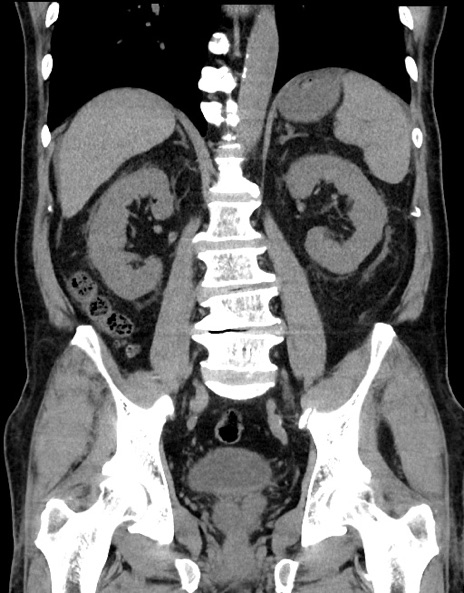

症例15(冠状断像)

【症例】70歳代男性

【主訴】腹痛

【現病歴】今朝から腹痛あり。全体的に痛い。特に左上の方。排ガスが今日はない。冷や汗が出る。

【既往歴】直腸癌術後

【身体所見】左側腹部〜上腹部に圧痛あり。腹膜刺激症状明らかなではない。軽度反跳痛。左下腹部に術後瘢痕あり。

【データ】WBC 7700、CRP 0.02